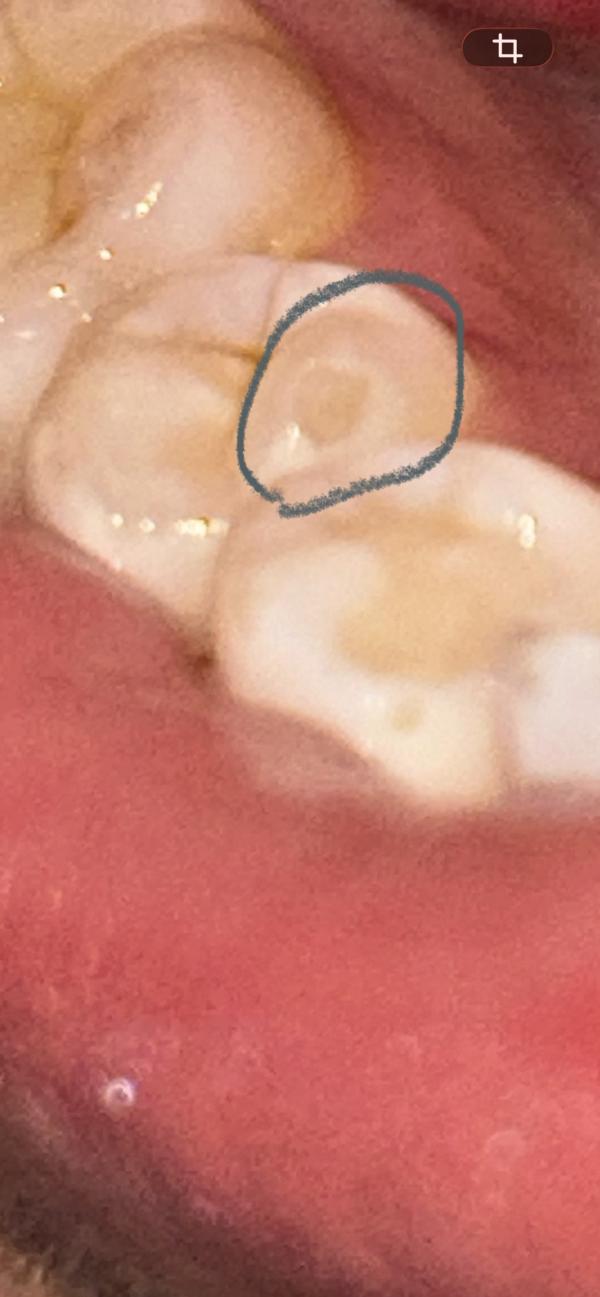

Почему крошатся зубы после пломбы: причины и что делать

Капец, вроде ничего не кушала

Но зубы немного раскрошился 🥺

Из за чего может быть?

Это из за того что прошло уже 2,5 года как поставила пломбу ?

Или все таки зуб